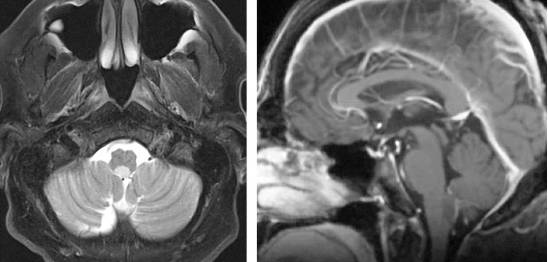

图3. 图示为向四脑室延伸和压迫的蚓部毛细胞星形细胞胶质瘤。肿瘤呈囊性,伴有明显强化的结节。囊壁未见强化,无需手术切除。

图4. 松果体细胞瘤在T2相上表现为高信号,伴有周围强化。松果体细胞瘤一般生长缓慢,偶尔需要手术干预。